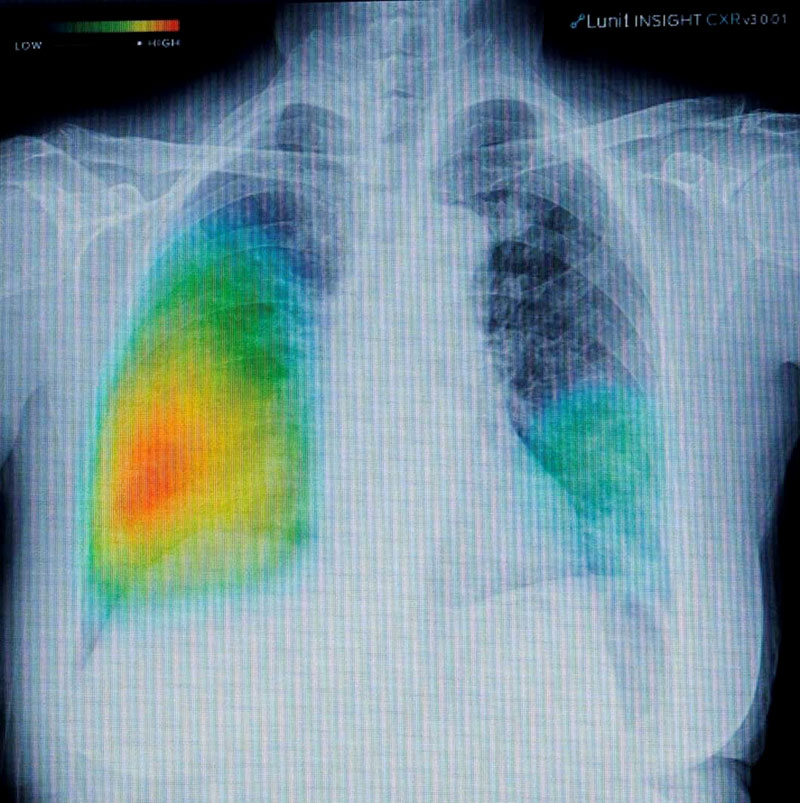

ดังนั้นการจะยุติการแพร่ระบาดของวัณโรคให้หมดได้ คือการค้นหาผู้ติดเชื้อให้เร็ว ด้วยการใช้มาตรการเชิงรุกเพื่อระงับการแพร่ระบาดของเชื้อ พร้อมทั้งใช้นวัตกรรมทางการแพทย์ที่ทันสมัย อย่างล่าสุดมีการดึงเครื่องเอกซเรย์ระบบดิจิทัลที่มีเทคโนโลยี AI มาใช้ในการวินิจฉัยร่วมกับวิธีการตรวจหาสารพันธุกรรมของเชื้ออณูจุลชีววิทยา (Molecular technique) ที่สามารถอ่านผลเอกซเรย์ได้ทันทีซึ่งต่างจากการวินิจฉัยผลแบบเดิมที่ใช้การเก็บตัวอย่างไปเข้าห้องแล็บเพื่อทำการวิเคราะห์ ซึ่งมีความล่าช้าและมีค่าใช้จ่ายสูง กว่าจะทราบผลเชื้อก็เกิดการแพร่กระจายไปมากแล้ว โดยกรมควบคุมโรคได้ตั้งเป้าหมายว่า ประเทศไทยต้องขยายการรักษาให้ครอบคลุมร้อยละ 90 ของผู้ป่วยภายในปี 2568 จากเดิมที่ทำได้เพียงร้อยละ 84”

มร.ยูโตะ คุมาไก ผู้ช่วยกรรมการผู้จัดการบริษัทฟูจิฟิล์ม (ประเทศไทย) จำกัด กล่าวว่า “เมื่อเร็วๆ นี้ เรายังได้ประกาศแคมเปญใหญ่ระดับโลก “NEVER STOP” เพื่อตอกย้ำความมุ่งมั่นในการเป็นส่วนหนึ่งที่ร่วมช่วยเหลือบุคลากรทางการแพทย์ ตลอดจนสถานการณ์วัณโรคในประเทศไทย ผ่านทางเทคโนโลยี ซึ่งเป็นนวัตกรรมสร้างสรรค์ของฟูจิฟิล์ม เราเดินหน้าพัฒนานวัตกรรมทางเทคโนโลยีอย่างต่อเนื่อง ประสานเทคโนโลยี AI เพื่อพัฒนาอุปกรณ์ทางการแพทย์ เช่น เครื่องเอกซเรย์ดิจิทัลเคลื่อนที่อย่าง FDR XAir และ FDR Nanoซึ่งเป็นเครื่องเอกซเรย์ดิจิทัลเคลื่อนที่ที่ใช้ในการวินิจฉัยวัณโรคปอดและสอดคล้องกับมาตรฐานเครื่องเอกซเรย์ที่องค์การอนามัยโลกแนะนำ (WHO) โดยสามารถช่วยบุคลากรทางการแพทย์วินิจฉัย และระบุตำแหน่งความผิดปกติในปอดได้อย่างรวดเร็วและแม่นยำ เพิ่มประสิทธิภาพทางการรักษาและลดอัตราการเสียชีวิต นวัตกรรมทางการแพทย์ของเราได้รับการยอมรับและนำไปใช้อย่างกว้างขวางในหลายพื้นที่ ในสถาบันทางการแพทย์ และโรงพยาบาลชั้นนำอย่างแพร่หลายทั่วโลก